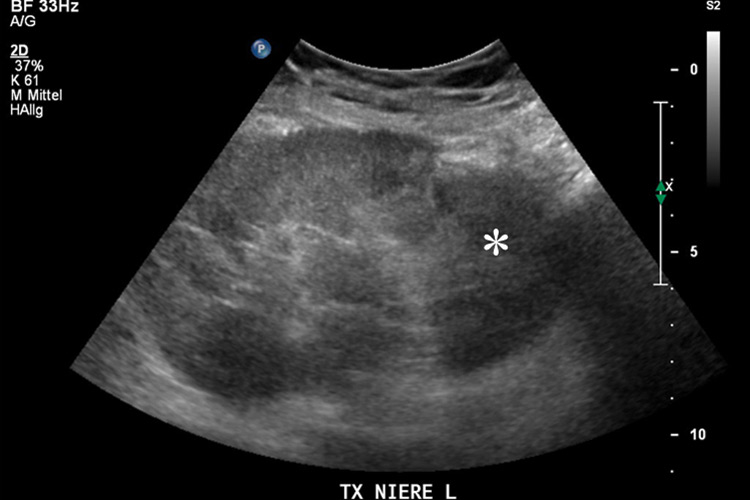

Figure 3

Transplanted kidney with hypoechoic region at the lower pole (*) on B-mode ultrasound (A). Corresponding CEUS imaging with devascularised region at the lower pole (*) in the transplanted kidney (B).

Furthermore, the use of CEUS has emerged as an excellent tool for assessing vascular complications of renal transplants by imaging the microcirculation similarly to that of the native kidney [39]. The sensitivity in the detection of transplant infarction is also very high (fig. 3). Due to the ability to image flow in the microcirculation, the infarcted size on CEUS may appear even smaller than on the corresponding colour Doppler ultrasound. Also cortical necrosis in renal transplants can be clearly depicted and is rendered more conspicuous by CEUS which allows a better immediate clinical management.